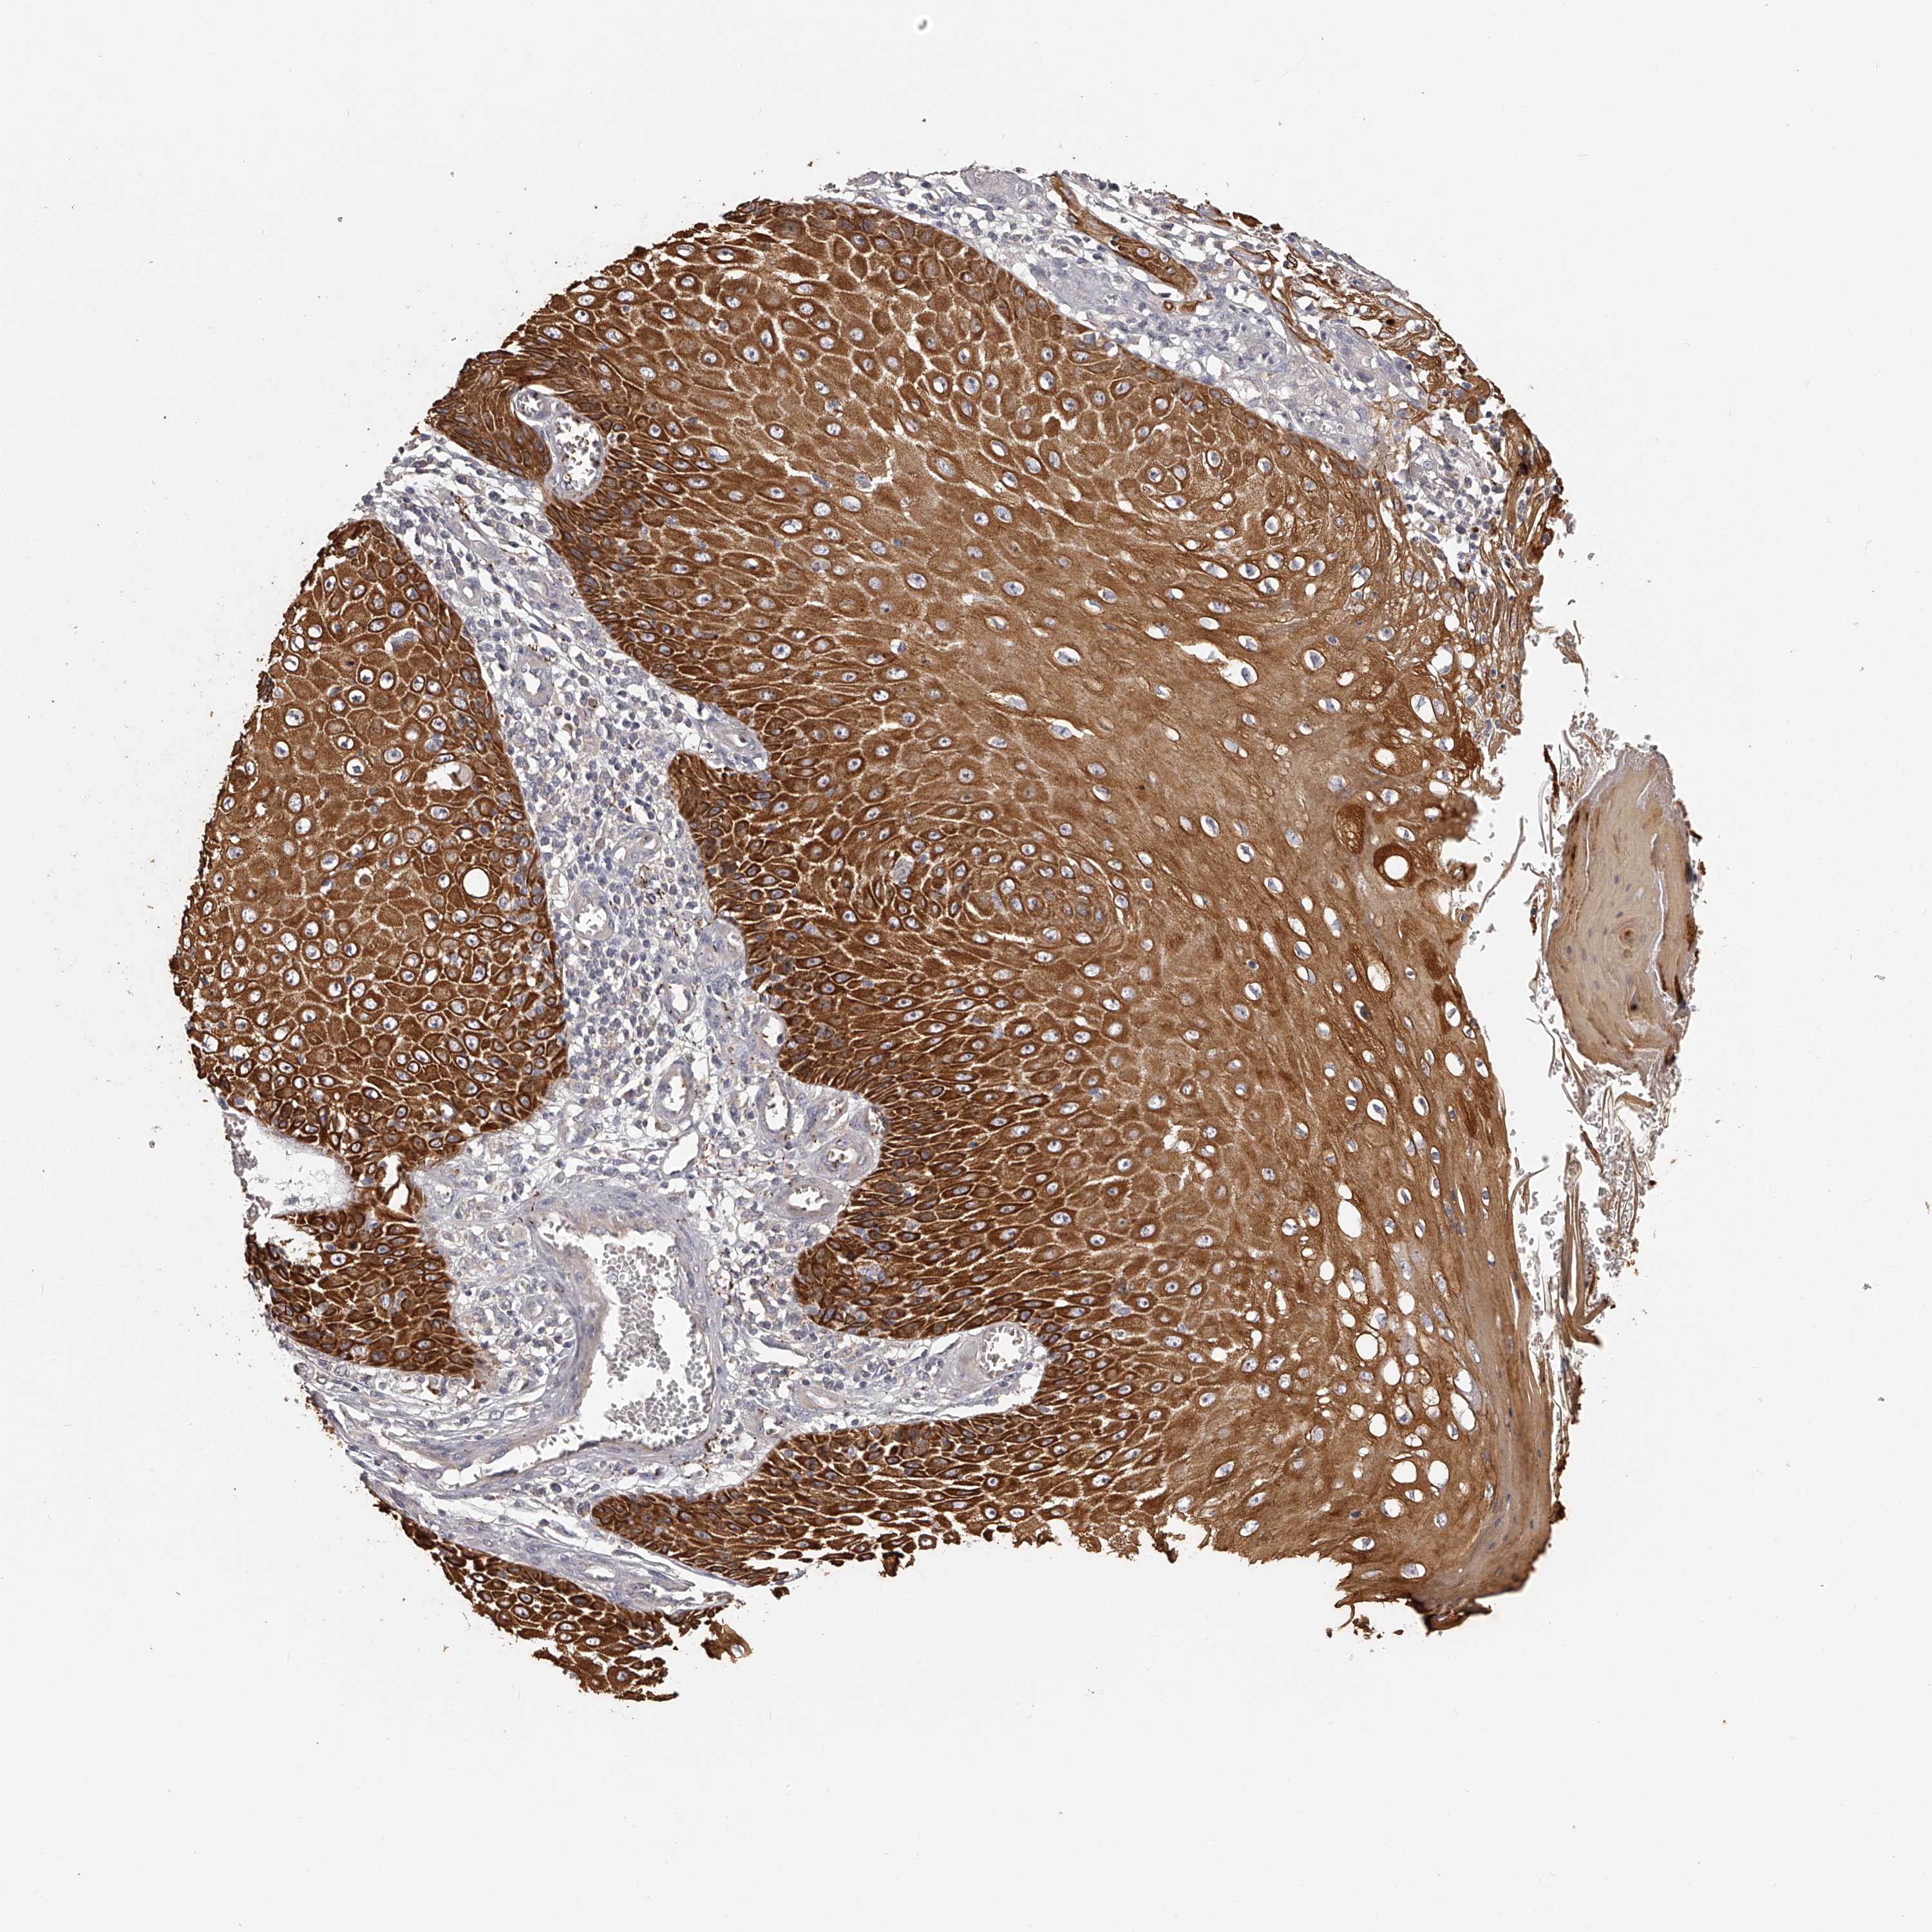

SKIN CANCER - Protein expressioni

A mouse-over function shows sample information and annotation data. Click on an image to view it in a full screen mode. Samples can be filtered based on level of antibody staining by selecting one or several of the following categories: high, medium, low and not detected. The assay and annotation is described here.

Antibody staining in the annotated cell types in the current human tissue is reported as not detected, low, medium, or high, based on conventional immunohistochemistry profiling in selected tissues. This score is based on the combination of the staining intensity and fraction of stained cells.

Each image is clickable and will lead to virtual microscopy that enables deeper exploration of all samples and also displays staining intensity scores, fraction scores and subcellular localization as well as patient and tissue information for each sample.

Antibody CAB010907

High

Strong

>75%

Cytoplasmic/membranous

Squamous cell carcinoma, NOS